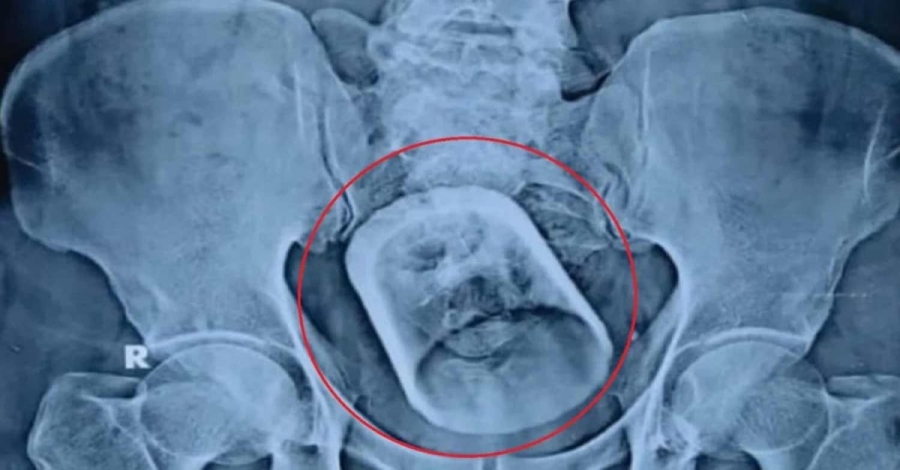

Ένας 55χρονος άντρας έφτασε στο νοσοκομείο υποφέροντας από οξεία δυσκοιλιότητα και έντονους πόνους στο στομάχι, με τους γιατρούς να τον εγχειρίζουν και να βγάζουν – τελικά – ένα γυάλινο ποτήρι από το παχύ έντερο.

Όπως αναφέρει η ιατρική γνωμάτευση του Δρ Μακχντουλούλ Χακ, του επικεφαλής των χειρουργών, οι ακτινογραφίες και ο υπέρηχος έδειξαν ότι κάτι είχε μπλοκάρει σοβαρά το πεπτικό σύστημα του ασθενούς.

Αρχικά, οι γιατροί της περιοχής Μπιχάρ στην Ινδία προσπάθησαν να αφαιρέσουν το ποτήρι τραβώντας το από τον πρωκτό με ενδοσκόπιο, «αλλά δεν δούλεψε. Έτσι χρειάστηκε να του ανοίξουμε την κοιλιά και να βγάλουμε το ποτήρι αφού προχωρήσαμε σε τομή του εντέρου» εξήγησε ο γιατρός.